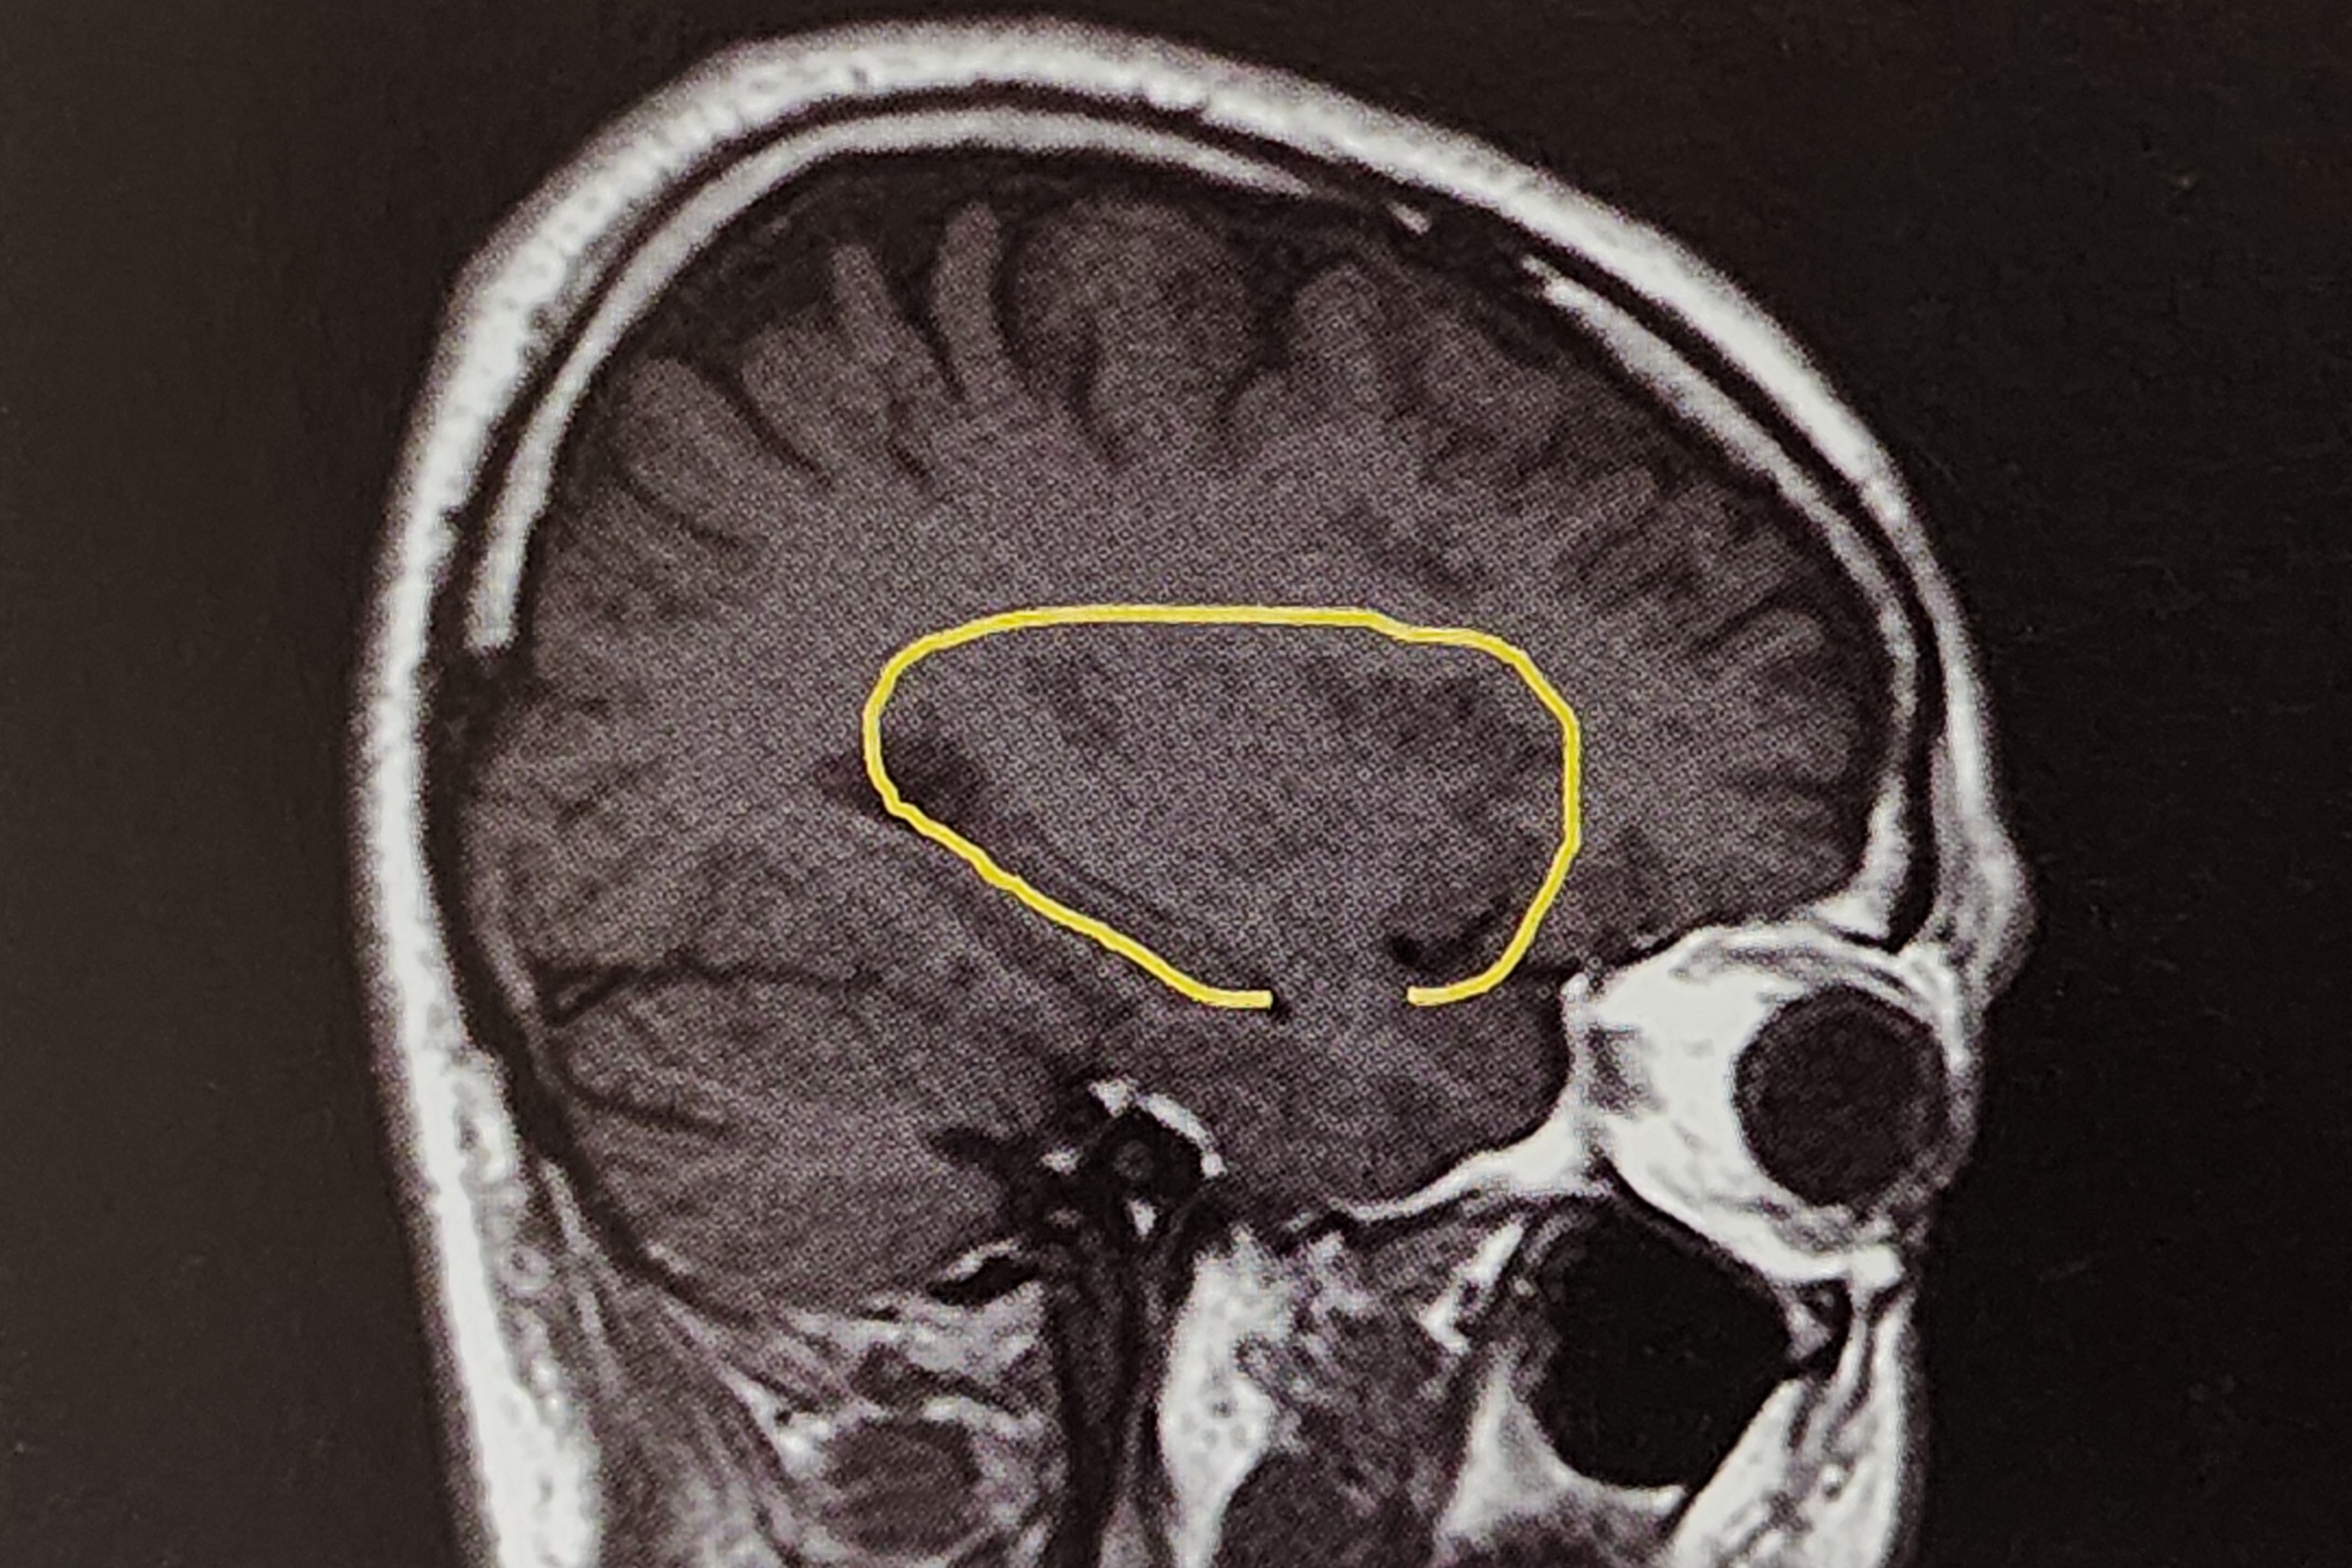

대뇌반구절제술(Hemispherectomy)은 난치성 뇌전증 치료를 위해 시행되는 가장 큰 수술 중 하나이다.

이 수술은 뇌전증 발작이 한쪽 대뇌반구 전체에 걸쳐 발생하는 경우에 적응증이 된다. 대표적인 적응증으로는 라스무센뇌염(Rasmussen’s encephalitis), 영아 편마비(Infantile hemiplegia), 반구거대증(Hemimegalencephaly), 미만성 반구 피질형성이상(Diffuse hemispheric cortical dysplasia), 스토지-웨버 증후군(Sturge-Weber syndrome), 거대 낭종(huge cyst) 등이 있다.

- MRI(Magnetic Resonance Imaging): 병변의 위치와 크기, 반대쪽 반구의 상태를 평가

- 총대뇌량절제술(Total Callosotomy): 대뇌반구를 연결하는 뇌량(Corpus Callosum)을 절단하여 양쪽 반구 간 신호 전달을 차단한다.